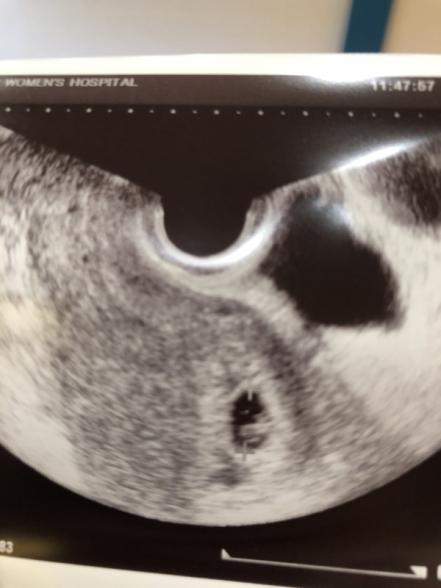

7週で見えた胎芽を添付しておきます。

7週3日の昨日 病院に行くと、胎嚢が13ミリになっていて 私には はっきり胎芽が見えましたが

医者は、胎芽とはまだ言えない なぁ。

少し点滅してるように見えるけど、13ミリで 心拍が見えた事は今までない 20ミリくらいにならないと 何とも言えない

出血もこんなにしてるから今出てきてもおかしくないのに、出てこないっていう事は 生きてるんだよなぁ。